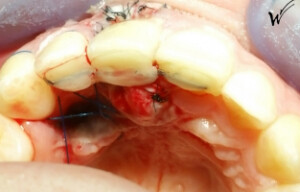

Lors de l’extraction, une greffe épithélio-conjonctive était nécessaire pour restaurer à la fois la hauteur du festonnage gingival et, bien sûr, les papilles gingivales qui disparaissent avec la dent extraite. J’ai choisi d’opter pour une greffe pédiculée avec un prélèvement au palais rétro-incisif.

L’utilisation de membranes de PRF (Plasma Riche en Fibrine) contenant des facteurs de croissance plaquettaires cicatriciels, ainsi que d’injections de PRP (Plasma Riche en Plaquettes), lors de l’intervention, renforce la capacité de reconstruction des tissus mentionnés précédemment. Ces protocoles modernes, constamment perfectionnés par les cliniciens, présentent des avantages majeurs pour la restauration immédiate de la microvascularisation, un élément déterminant pour une cicatrisation optimale à long terme des tissus mous et durs.

L’implant a été positionné dans l’alvéole, aligné avec la racine. À ce stade, un guide chirurgical peut s’avérer extrêmement utile, en particulier pour éviter d’éventuels obstacles anatomiques, tels que des paquets vasculo-nerveux situés dans le trou rétro-incisif.